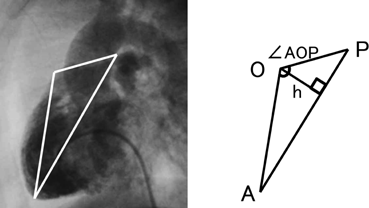

We applied a geometric method to clarify the morphology of the right ventricular outflow tract. Using the lateral view of right ventriculography on cardiac catheterization, we defined 3 fixed points on the anterior face from the right ventricular apex through to the main pulmonary artery at the timing of end-diastolic phase. Point “A” was on the apex of right ventricle and point “P” was on the main pulmonary artery at the right/left bifurcation. These two fixed flow points are not affected by the degree of anterior prominence of the right ventricular outflow tract. Point “O” was the most prominent point which could get maximum distance from AP on the right ventricular outflow tract (Fig. 1). We made geometric measurements on a triangle defined as AOP. The length of AP, AO, and OP were measured. Also the height “h” of the triangle from base AP to point O, and the angle “∠AOP” was measured as the value representing the degree of anterior prominence of the right ventricular outflow tract. Similar measurements were done on VSD hearts. The results were compared between the tetralogy of Fallot (TOF group, n=51) and ventricular septal defect groups (VSD group, n=34).

Median age at the study was 362 days in the TOF group (range, 47–1157 days), and 237days in the VSD group (range, 47–2533 days). Height and body weight of each group was 71.0 cm (range 50.2–84.2 cm) and 8.5 kg (range 2.8–12.2 kg) in the TOF group, 69.4 cm (range 55.3–114.0 cm) and 7.9 kg (range 4.1–21.3 kg) in the VSD group (Table 1). These differences were not found to be significant. Actual length of AP, which stands for the distance of a straight line from the apex of right ventricular to the main pulmonary artery at bifurcation, was 60.3 mm (range 44.3–84.5 mm) in the TOF group, which was significantly shorter (p<0.001) than the 63.7 mm (range 26.3–99.9 mm) measurement in the VSD group. Length of AO, which stands for the distance of a straight line from the apex to the most prominent point of right ventricular outflow tract, was 44.4 mm (range 28.7–62.0 mm) in the TOF group which was shorter (p<0.001) than the 51.3 mm (range 22.1–84.4 mm) in the VSD group. The quantity of the differences between the groups was very small, however they were obvious. Length of OP, which stands for the distance of a straight line from the most prominent point of right ventricular outflow tract to pulmonary bifurcation, was 26.3 mm (range 15.9–40.9 mm) in the TOF group and 28.3 mm (8.9–37.5 mm) in the VSD group and no significance was found in this difference (Table 2). Scatter diagrams of actual values of the AOP triangle of both groups are shown in Fig 2. Since the length of AP, which is the base of triangle AOP, differs in each group, we utilized the length of AO and OP proportional to AP to compare the geometric shape itself of the AOP triangle between the groups. Points A and P were the two fixed points which we defined as a point which would not be affected by the degree of anterior prominence of the right ventricular outflow tract. Relative length of AO for AP (relative AO=AO/AP) was 0.73 (range 0.56–0.91) in the TOF group and this was significantly smaller (p=0.004) than the 0.78 (range 0.70–0.86) value in the VSD group. Relative length of OP for AP (relative OP=OP/AP) was 0.44 (range 0.33–0.59) in the TOF group which was longer (p<0.001) than the 0.41 (range 0.28–0.48) result in the VSD group (Table 3). We also investigated the height h and angle ∠AOP to determine how prominent the right ventricular outflow tract is in the tetralogy of Fallot. Relative length of h for AP (relative h=h/AP) was 0.30 (range 0.19–0.41) in the TOF group and 0.29 (range 0.21–0.36) in the VSD group which was not found to be significant. Angle ∠AOP in the TOF group was 112.5° (range 96.2–134.8°) and 112.5°(range 98.6–126.3°) in the VSD groups; this difference, even though the ranges varied, was not found to be significant (Table 3). Fig. 3 shows the complete schema of triangles representing the architecture of the right ventricular outflow tract in both the TOF and VSD groups. The difference in geometric shapes of triangles between the groups was insignificant.